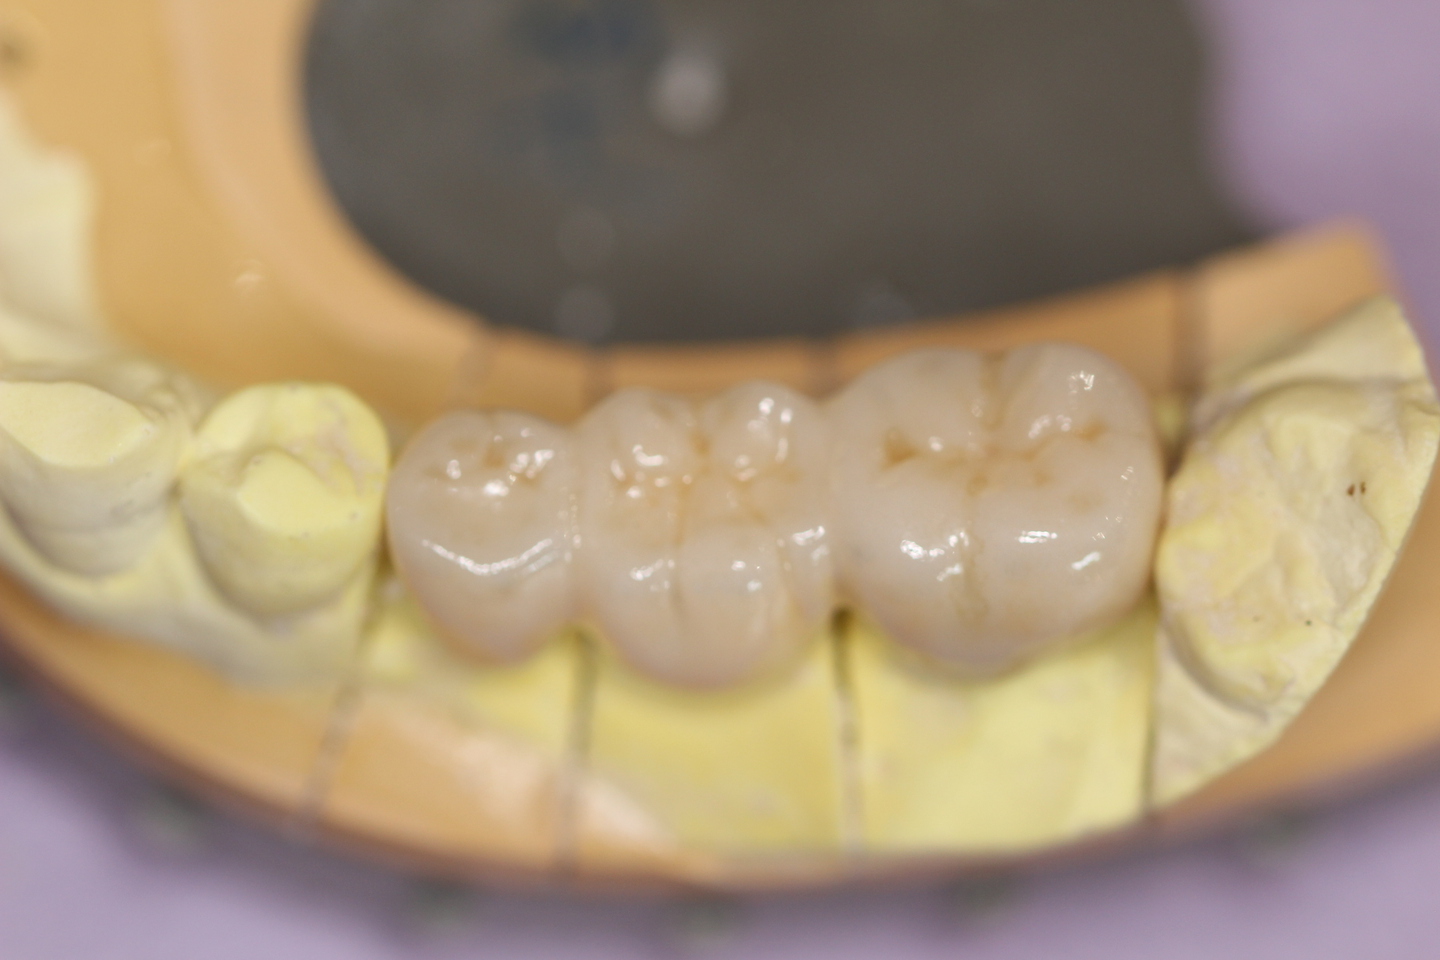

オールセラミック

ジルコニアは人口ダイアモンドとして有名で、宝飾品にも使われているため女性の方はご存知かもしれません。

宝飾品に使用されている物(キュービックジルコニア)と口腔内に使用されているジルコニア(フインセラミック)は、結晶構造が違いますが基本的には同じ物です。

生体に優しいため、人口関節にも使用されています。

強度があり、美しく、金属を一切使用しないので、金属イオンの流出がなく生体親和性があり安全性が高いと言えるでしょう。

従来からある金属にセラミックを焼き付けたメタルボンドクラウン も美しいですが、内面に金属を使用しているので、ジルコニアの方が生体には優しいと言えます。

ただしすべての症例に適応とは言えないので、ご相談ください。